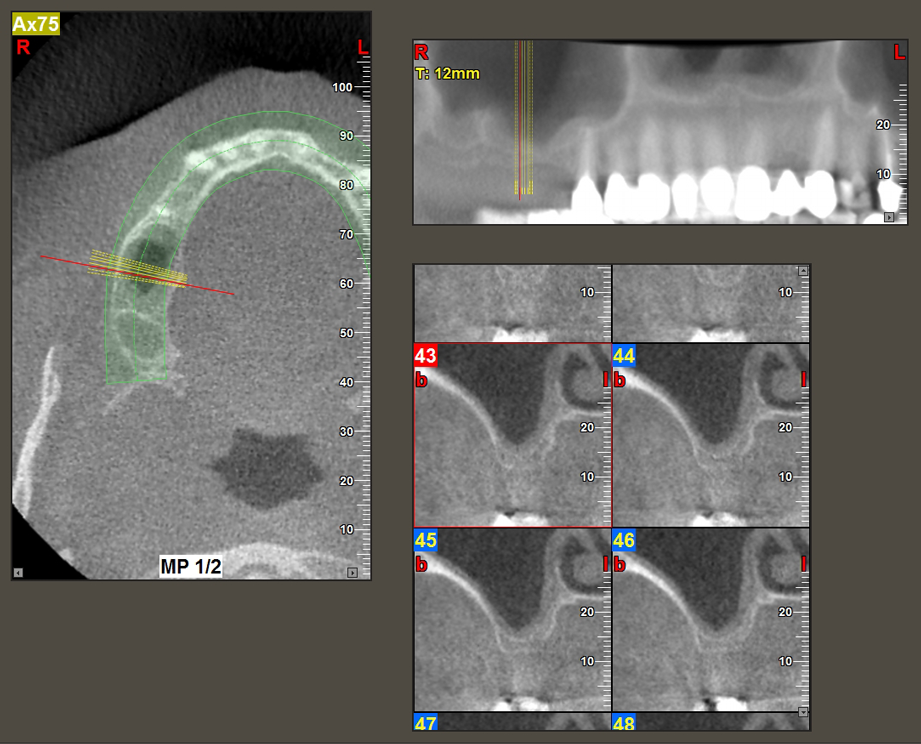

Following atraumatic preparation of the mucoperiosteal flap, the implant position was marked with the I1 instrument and the site prepared – until initial resistance was felt. Piezosurgical instruments were used in an up and down movement without any pressure being exerted. The piezoelectric vibration produced the desired and efficient cavitation.

The I2A instrument (diameter 2.0 mm) was then used to perforate the sinus floor intermittently and on the smallest scale possible. This special piezosurgical method ensures that the Schneiderian membrane is not damaged. When the Z25P was used, the membrane was already lifted slightly by the coolant supplied via the instrument tip (Fig. 3). The coolant quantity was just 50% in order to avoid high pressure in the implant bed.